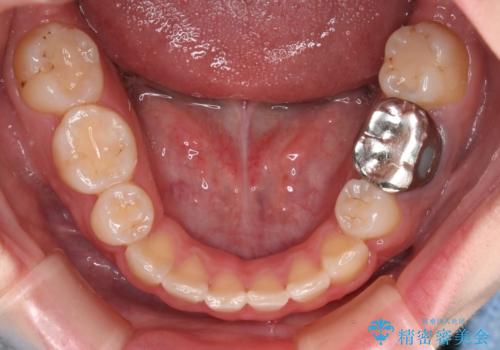

- 前歯のガタつきと口元の改善を主訴に来院されました。

なるべく目立たない装置が良いというご要望と、口元を引っ込めたいというご要望を両方達成するために今回はハーフリンガル装置を選択し治療計画の立案を行いました。